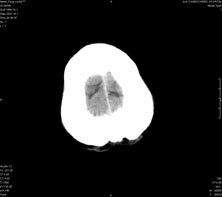

男,41岁,间断抽搐1小时,失神5分钟,bp130/90mmhg。低密度区ct值约16hu。

脑实质见多发散在的钙化点,左顶叶见一囊变灶,多考虑脑囊虫。

多发的囊泡(多发囊型)+多发的钙化(慢性钙化型)=混合型

多发脑囊虫—混合型!活动期